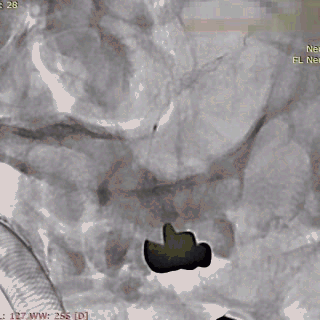

第二枚3*25支架沿017支架微导管上高。

第二枚支架远端释放。

第二枚支架释放至中段。

中段释放适当推挤系统,保持贴壁良好。

中段释放后造影。

继续释放支架。

继续释放支架,造影观察贴壁良好。

完全释放支架。

支架微导管沿推送导丝上高并将推送导丝撤出。

术后即刻造影。

术后重建。